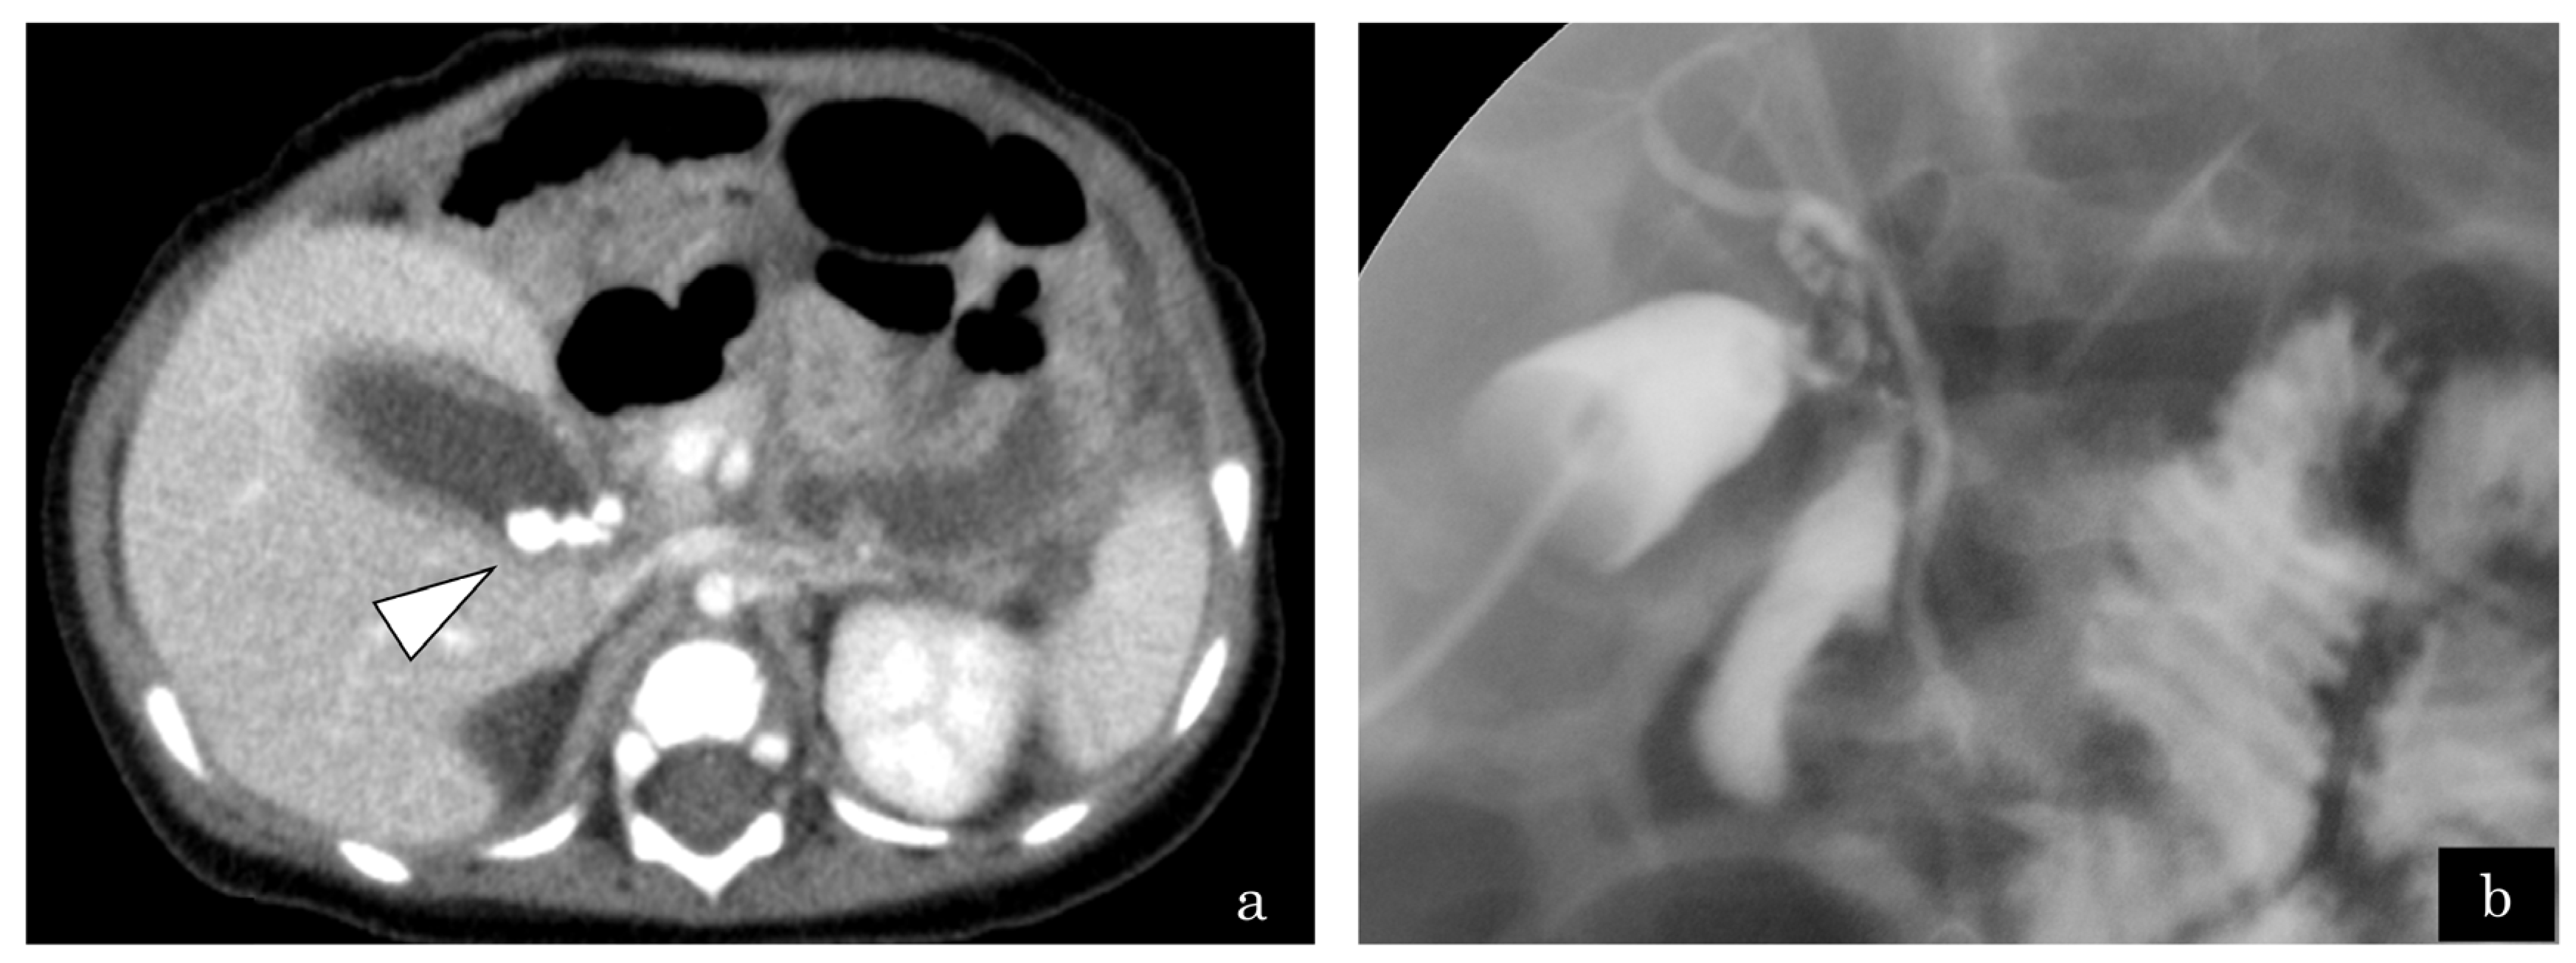

A 4-month-old girl presented with vomiting, and US revealed gallbladder stones. Computed tomography demonstrated multiple gallbladder stones and gallbladder wall thickening (Figure 2a). The patient presented with shock, thereby prompting emergency gallbladder drainage. Intraoperative cholangiography demonstrated no communication between the bile and pancreatic ducts (Figure 2b). Lipase in bile juice from gallbladder drainage was persistently high (Figure 3), which indicated that PBR recurred persistently. ERCP exhibited that the CC was 2.2 mm; however, the SO segment could not be measured because of the patient’s small size. She underwent bilio–jejunal anastomosis, with an uneventful clinical course postoperatively.

Figure 2.

Case 6: A 4-month-old girl presented with vomiting and revealed gallbladder stones on ultrasonography. (a) Enhanced computed tomography revealed multiple small gallstones and gallbladder swelling (white arrowhead). (b) The patient developed septic shock due to cholangitis. Emergency gallbladder drainage was performed. No communication between bile and pancreatic duct was observed by cholangiography.